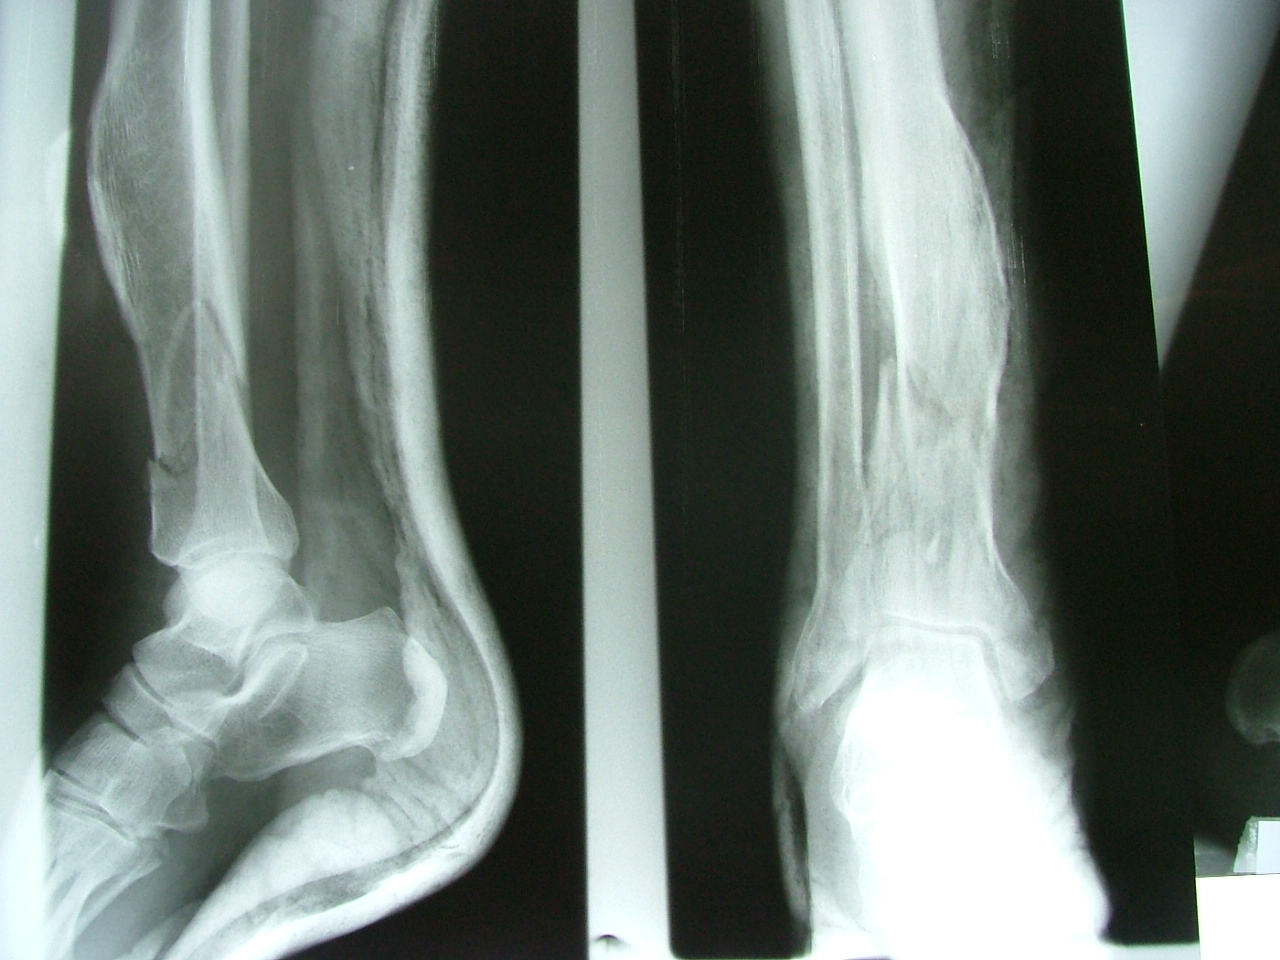

تهیه و تامین تجهیزات ارتوپدی و مشارکت در انجام اعمال جراحی ارتوپدی و عمل‌های نادر عضو تیم جراحی افزایش قد -جهت ترمیم شکستگی های قدیمی و جوش نخورده گی ها -طویل کردن اندامها- طویل کردن انگشت قطع شده - تعویض مفصل لگن _تعویض مفصل زانو _ بازسازی رباطACLوPCL_اصلاح ناهنجاریهای مادر زادی -با همکاری پزشکان و متخصصان مجرب آموزش دیده در روسیه و اتریش و سوئیس بروش جراحی ایلیزاروف و lon و lsa و واگنر و اسلایدینگ نیز جدید ترین روش افزایش قد و اندام در سال 1397 بنام hil هیل برای اولین بار- افزایش قد به 6 روش جراحی و جدیدترین روش در اروپا و روسیه. آدرس مطب _تهرانسر بلوار اصلی مجتمع سهند طبقه4 واحد 410

تهیه و تامین تجهیزات  ومشارکت در انجام اعمال جراحی  ارتوپدی

-جهت ترمیم شکستگی های قدیمی و جوش نخورده گی ها -

طویل کردن اندامها- طویل کردن انگشت

-اصلاح ناهنجاریهای مادر زادی

باهمکاری پزشکان و متخصصان مجرب بروش جراحی ایلیزاروف